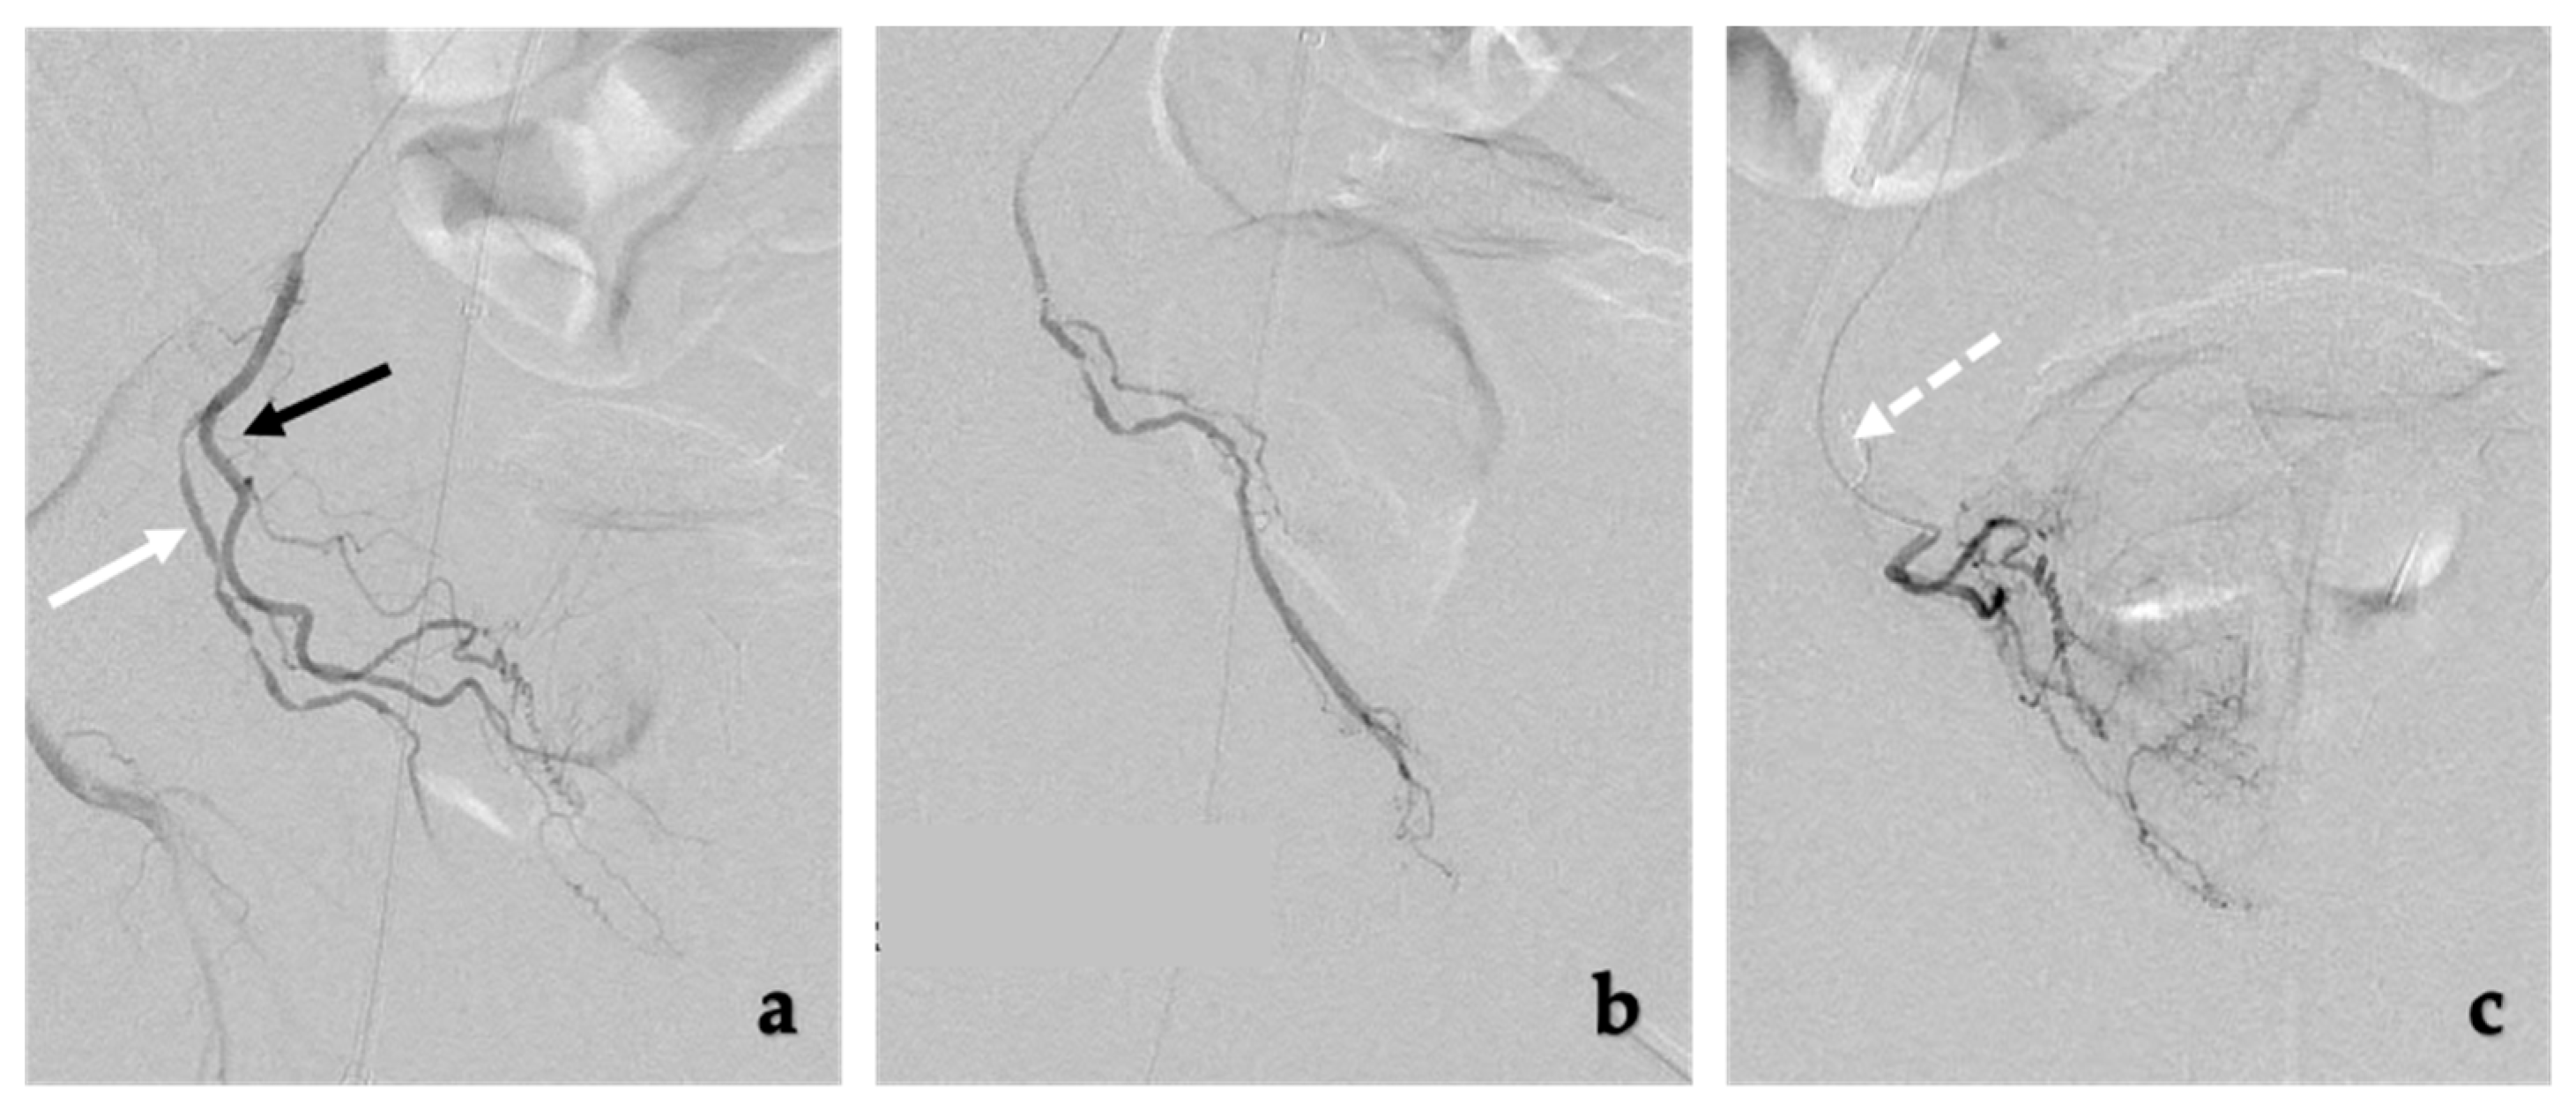

The prostate arteries are very small and prone to vasospasm upon manipulation [43]. Nitroglycerin should be readily available on the Table 2 and can be given intra-arterially as needed. Additionally, coil embolization may need to be performed of any non-target arteries, generally to the rectum or penis (Figure 3). Coil embolization may be needed in about 26% of all cases and can prevent particles from distal embolization [57].

Figure 3.

Coil embolization of extra-prostatic arteries. (a) The middle rectal artery (white arrow) and prostatic artery (black arrow) share a common trunk with short distance between middle rectal artery and prostatic artery. To safely embolize the prostatic artery with particles, the middle rectal artery can be embolized with coils, (b) Selective injection of the middle rectal artery prior to coil embolization, (c) DSA imaging of the prostatic artery after coil embolization (white dotted arrow) of the middle rectal artery shows filling of the prostate without filling of the rectum. Following these steps, the prostatic artery can now safely be embolized with particles.